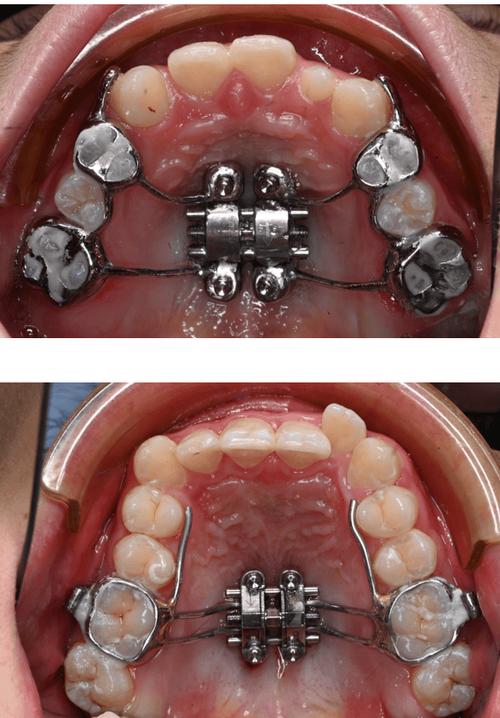

扩弓技术:解决牙弓宽度不足

针对牙弓狭窄病例,扩弓技术是关键:

- 快速扩弓(RME):通过上颌腭中缝处的扩弓装置,短期内(1-2周)打开腭中缝,增加上颌牙弓宽度,适用于青少年患者(骨骼可塑性强);

- 慢速扩弓:通过螺旋扩弓器,每月1mm的速率扩大牙弓,适用于成人轻度狭窄或牙弓宽度不足。